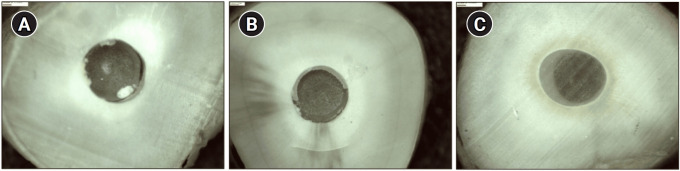

Abstract Image